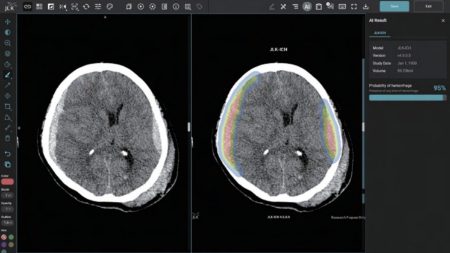

JLK-ICH는 환자의 뇌 CT 영상을 분석해 뇌출혈 영역을 검출하는 AI 솔루션이다. 통상 뇌졸중 의심 환자가 응급실에 도착하면 가장 먼저 뇌 CT를 촬영해 뇌출혈 여부를 확인하는데 이 과정에서 JLK-ICH가 활발히 적용될 것으로 점쳐진다. 특히 기존에 획득한 JLK-LVO, JLK-CTP, JLK-PWI와 함께 연동돼 전 주기에 걸친 뇌졸중 진단과 치료 결정 활용 시너지는 물론 미국 병원에서의 시장 차별성과 경쟁력이 매우 향상될 것으로 업체는 기대하고 있다.

혈관이 막히는 뇌경색 대비 중증도가 높은 뇌출혈은 출혈 크기 증가 우려와 재출혈 위험으로 치료까지 걸리는 시간을 단축하는 것이 환자 예후 개선에 필수적이다. 제이엘케이 관계자는 "JLK-ICH는 임상 연구를 통해 발생 특징이 다른 5가지 뇌출혈 유형에 대해 편차 없는 높은 검출 성능을 입증했다"며 "골든타임 확보에 큰 역할을 할 것으로 기대된다"고 말했다.